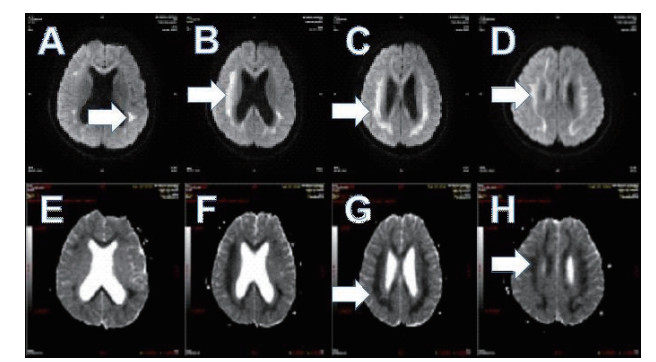

2 结果 2.1 基本资料及头颅核磁特征本观察研究最终纳入患者51例,中毒患者的头颅核磁特征表现为:在MRI的常规序列(T1\T2\FLAIR)病灶显示不明显,但在DWI表现为高信号,ADC值下降呈低信号。病变部位主要是胼胝体的压部(所有阳性病例胼胝体压部均受损),病变也可以形成以胼胝体为中心的广泛白质病变,皮质不受损害。见图 1,2。

| 图 1 A.T1序列/B.T2序列/C.FLAIR序列均无异常;D.DWI系列上为高信号(箭头所示) |

3 讨论氟乙酰胺进入人体后生成氟柠檬酸, 可在脑组织诱发细胞毒性脑水肿[4]。细胞毒性脑水肿在DWI上呈现高信号,在ADC上呈低信号,结合我们发现佐证氟乙酰胺中毒所引起的脑部病变性质是细胞毒性脑水肿,并且证实氟乙酰胺中毒病变部位主要是胼胝体的压部,病情危重者可出现以胼胝体为中心的广泛白质病变,皮质不受损害。所幸此病变特点符合可逆性胼胝体压部病变综合征(reversible splenial lesion syndrome,RESLES)[5]:是一种由各种病因引起的累计胼胝体压部的临床影像综合征。其特点为MRI上可见胼胝体压部(SCC)的卵圆形、非强化病灶,一段时间后可完全消失[6]。